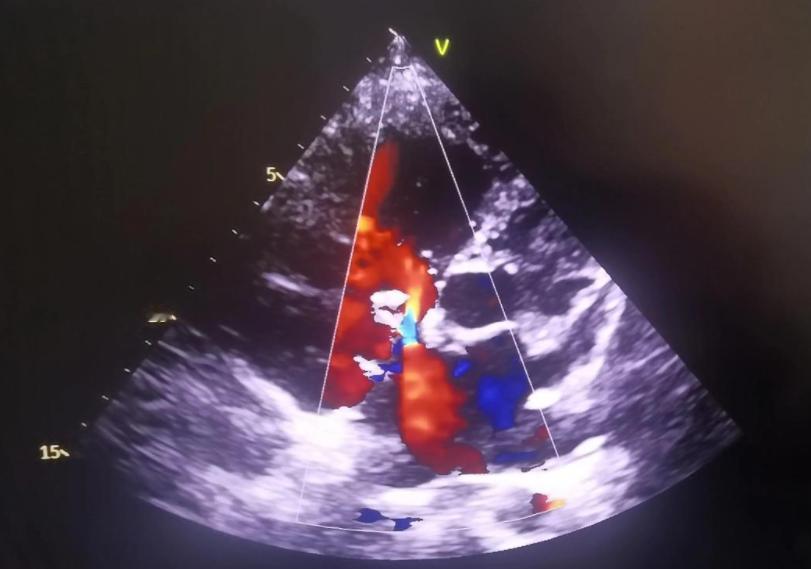

有人说:“我又没胸痛,查啥?”但心衰早期哪有典型症状?可能就是容易疲劳、稍微动一动就气短、夜里总想坐起来透口气。这些信号太模糊,谁都会归结为“年纪大了”或者“最近累着了”。可左心室肥厚、瓣膜反流这些结构性变化,早在症状冒头前好几年就已经在彩超上露馅了。

根据《中国心力衰竭诊断和治疗指南》,超声心动图是诊断心衰的金标准之一。它能精准测量射血分数(EF值),这是判断心脏泵血能力的核心指标。正常人在50%以上,一旦低于40%,就属于明显心功能下降。而这个数值,光靠听诊、心电图根本摸不准。